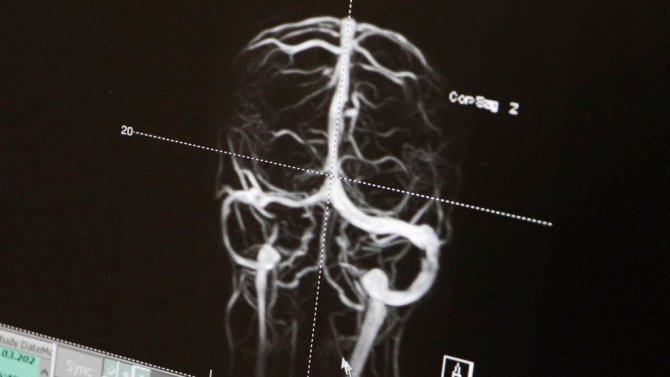

Hastalığın erken tanı konulmayıp uygun tedavisinin yapılmadığında geri dönüşümsüz körlüğe yol açtığını belirten Dr. Öğr. Üyesi Hülya İnce, "Psödotümor serebri; kafa içerisinde herhangi bir yer kaplayan lezyon olmadığı halde, sanki bir kitle varmış gibi, beynin basıncının artışı olarak tanımlanır. Nasıl ki göz tansiyonu, dolaşım sisteminin tansiyonu varsa, kafa içindeki yapıların anormalliğine bağlı beynimizin de tansiyonu yükselebiliyor. Biz de çocuk nöroloji uzmanı olarak, öncelikle kafa içerisinde vasküler, tümoral ya da herhangi yapısal bir lezyon var mı diye beyin MR ile değerlendiriyoruz. MR venografi dediğimiz bir yöntemle, beynin toplar damarlarında kan akımında bir anormallik olup olmadığını araştırıyoruz. Uygun hastalarda, beyin omurilik sıvısının (BOS) basıncını ölçerek, yüksek olup olmadığını değerlendiriyoruz. Özellikle doğurganlık çağındaki obez kadınlarda sık görülen bu hastalığın çocuklarda da çok sık olduğu bilinmektedir. Son 5 yıllık meslek hayatımda 45 tane olguya tanı ve tedavi uyguladım. Bu olguların 24'ü kızdı, 21'i ise erkekti ve ortalama 9 yaş civarlarında bize başvurduğunu gördük. Bu hastalarımızın en sık şikayeti baş ağrısıydı. Geniş bir nedensel tarama testleri uyguladığımız bu hastalarımızın yüzde 92'sinde etiyolojik bir sebep bulduk. Bu sebepleri ortadan kaldırarak ve uygun tedaviyi erken dönemde başlayarak hastalarımızın hiçbirini cerrahiye göndermedik. Hepsini ilaç tedavisiyle iyileştirdik. Bu çok büyük önem arz ediyor. Psödotümor serebri dediğimiz hastalığın en korkutucu yönü, geri dönüşümsüz körlük oluşturmasıdır. Bu yüzden eğer tanıda geç kalırsak, ilaç tedavisini iyi yapamazsak ve etiyolojik nedenleri ortadan kaldıramazsak hastalarımızı körlükten kurtaramayız. Maalesef ki, görme sinirindeki kalıcı hasara bağlı olarak gelişen görme kaybı yeniden elde edilemez. Bu nedenle uygun tedavi edilmeyen çoğu hasta cerrahiye sevk edilebiliyor. Buradaki en büyük avantajımız, geniş etiyolojik testleri tüm hastalarımıza uygulayarak altta yatan nedeni ortaya koymamız oldu. Hastamız Elisa özelinde düşünürsek, bu etiyolojik testler sonucunda hastamızın beyin toplar damalarında bir pıhtı olduğunu gördük. Genetik olarak da pıhtı oluşumuna yol açan bir faktörün hem anneden hem babadan Elisa'ya aktarıldığını saptadık. Çocuk Hematoloji departmanımızla birlikte önce trombolitik, sonra da antitrombotik koruyucu tedavi ile hem kafa içinde artmış basıncı düzelttik, hem de pıhtıyı erittik" diye konuştu.